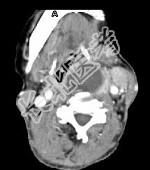

- 单项选择题女,64岁, 发现双甲状腺肿大1月余,CT如图所示, 最可能诊断是 ( )

A、甲状腺腺瘤

B、结节性甲状腺肿

C、甲状腺结核

D、甲状腺癌并淋巴结转移

E、甲状腺转移瘤